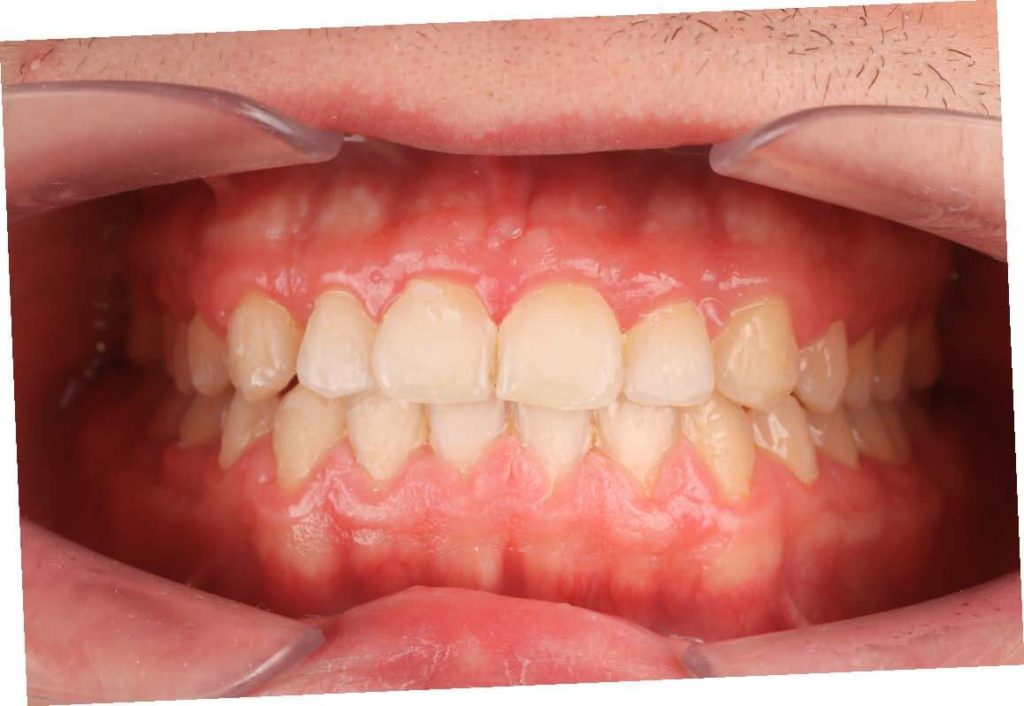

SITUACIÓN FINAL

Resultados y conclusiones

Se resuelve el apiñamiento, la relación entre los caninos y los molares de clase I, y se estabilizan el overjet y el overbite. Corrección del desplazamiento de la línea media. En el paso final se realizó un blanqueamiento y restauraciones directas en los dientes 12 y 22 .

Colocamos retención fija en el maxilar inferior y retenciones removibles tanto en superior como en inferior.